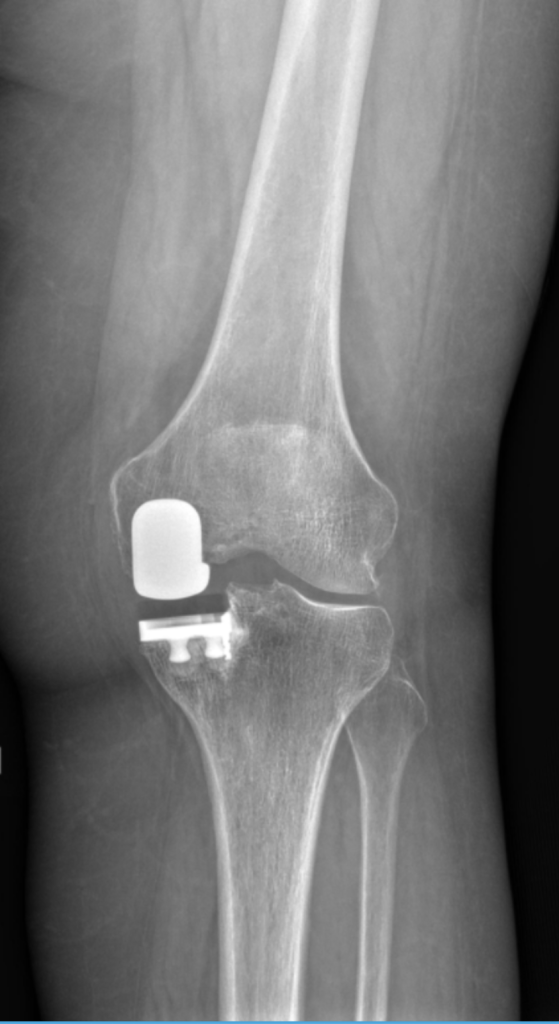

Dr. Movassaghi removes only the damaged portion of the joint and replaces it with a small metal and plastic implant, leaving the healthy bone, ligaments, and cartilage intact. Robotic assistance ensures perfect implant alignment and natural motion.